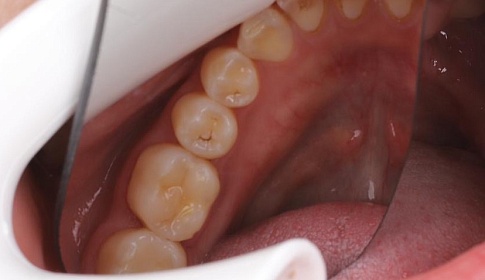

Поверхностный кариес

При поверхностном кариесе, который возникает как следствие кариозного пятна, участок зуба становится чувствительным и шероховатым. Без бормашины тут уже не обойтись. Процедура лечения проходит в несколько этапов:

- очищается налет;

- производится препарирование пораженной области;

- участок обеззараживание;

- выполняется процедура реминерализации;

- устанавливается пломба;

- участок выравнивается.

Процедура обычно доставляет минимум дискомфорта, потому что кариозная полость неглубокая.